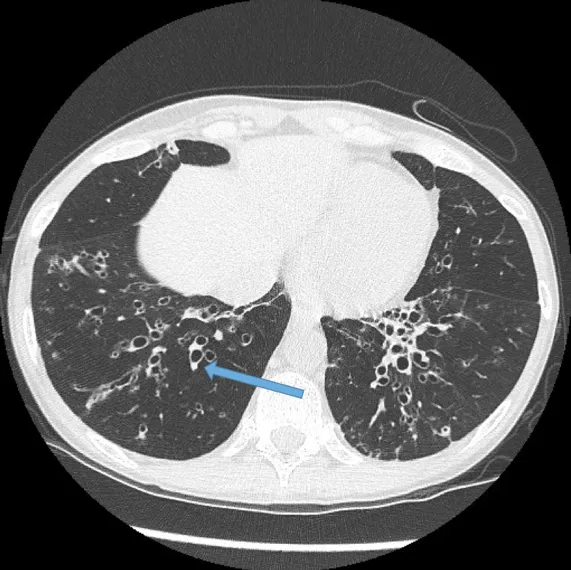

- High-Resolution CT (HRCT) is key.

- Shows "tram tracks," signet ring sign (bronchus > artery).

⭐ Exam Favorite: The "signet ring sign" on HRCT is the key diagnostic finding. It represents a dilated bronchus immediately adjacent to its smaller accompanying pulmonary artery branch.

- High-resolution CT (HRCT) is the diagnostic gold standard, revealing characteristic "tram track" and "signet ring" signs.